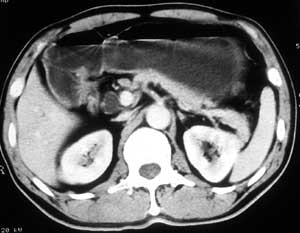

患者,男,57岁,梗阻性黄疸10余天。

这个病例胰头无明显增大,胆总管扩张明显而肝内胆管扩张更不明显,病程较短,

注意到十二指肠乳头明显突出,但尚光滑。分析以下可能性:

1、十二指肠乳头本身的病变,如乳头炎症;

2、急性乳头水肿,胆总管下端结石排石后乳头水肿;

3、壶腹部胆总管下端肿瘤累及十二指肠乳头。

十二指肠乳头粘膜慢性非特异性炎症